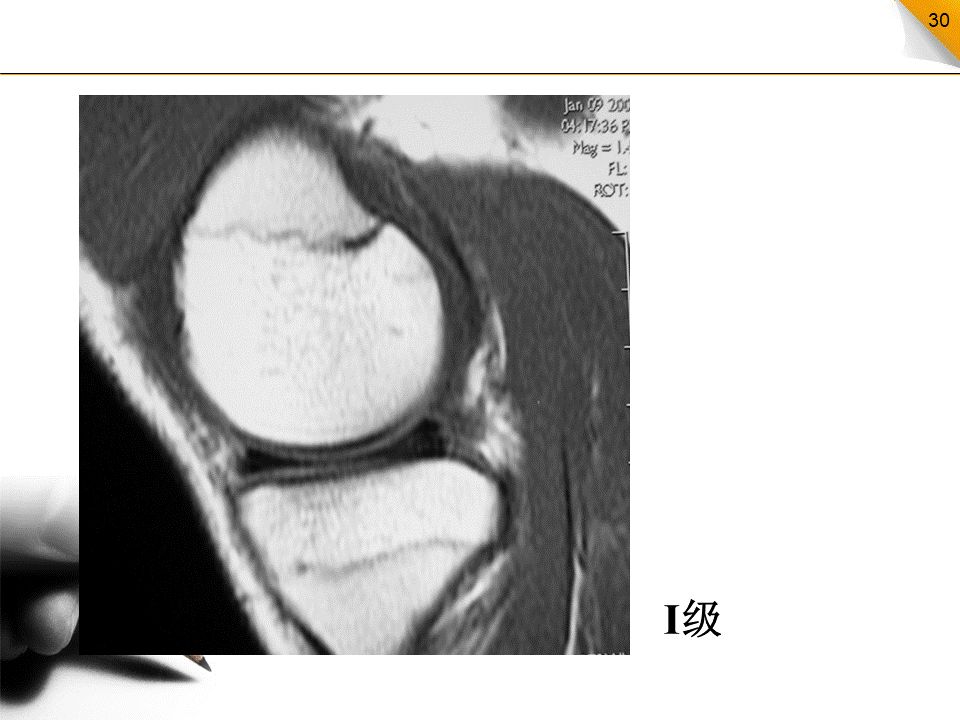

半月板损伤的MR分级

0级:正常半月板,均匀的低信号,形态规则I级:不与半月板关节面相接触的灶性信号增高影II级:半月板内线性信号增高,可延伸至半月板的关节囊缘,但未达到半月板的关节面缘,是I级信号改变的继续,范围更广III级:半月板内的高信号达到半月板的关节面,代表半月板的撕裂IV级:半月板破碎成多块并向关节腔内移位